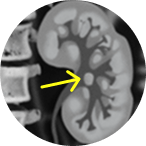

Jelmyto® (mitomycin) for pyelocalyceal solution is indicated for the treatment of adult patients with low-grade Upper Tract Urothelial Cancer (LG-UTUC).

This portrays real-world scenarios in which JELMYTO was used in a diverse range of tumor types. UroGen's Olympus trial studied patients with treatment-naïve or recurrent LG-UTUC with ≥1 measurable papillary tumor 5 to ≤15 mm located above the ureteropelvic junction (tumor debulking was permitted prior to study enrollment for tumors >15 mm).1 For additional inclusion and exclusion criteria, please see the Olympus trial study design.